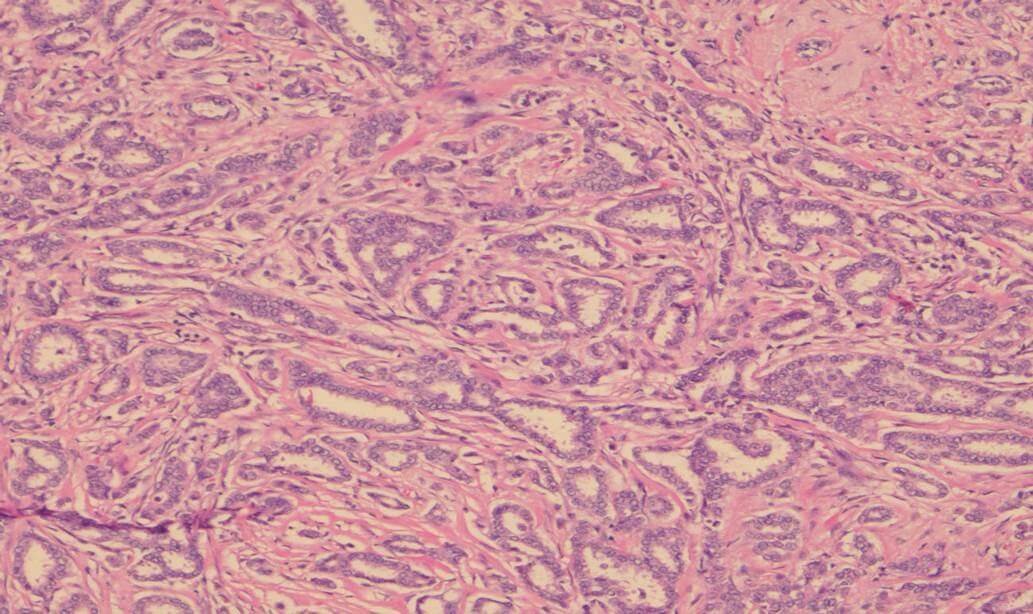

Invasive carcinoma is most commonly ductal carcinoma of no special type, with invasive lobular carcinoma the next most common. Invasive lobular carcinoma may show more extensive disease than appreciated clinically, or on imaging pre-operatively, and it is useful for this identification to assist with planning surgery. Tumour grade is a measure of tumour differentiation and is an important prognostic variable that influences decisions about additional treatment such as chemotherapy. Grading takes into account the ability of the tumour to make glands, the degree of nuclear pleomorphism and the proliferative rate measured by counting mitoses (Figure 1 – grade 1 invasive carcinoma, Figure 2 – grade 3 invasive carcinoma).

![This image depicts grade 3 invasive carcinoma. Professional medical imaging for clinical reference and educational purposes. [umbracoNodeId=9798]](/assets/image/jpeg/grade-3-invasive-carcinoma-6f05id2oxges3xhbeoh5pv.jpg)

Figure 2: Grade 3 invasive carcinoma